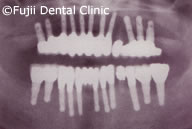

ヘビースモーカーであったために、禁煙してもらい、歯のクリーニングやブラッシング指導後、およそ2年間かけて左上犬歯と左下第一小臼歯以外すべての歯を抜歯し、インプラントの埋入手術を行いました。左右上顎臼歯部はサイナスリフトなどを併用し、インプラントによる咬合の再構築を試みました。

| 術後パノラマ写真および口腔内写真 |